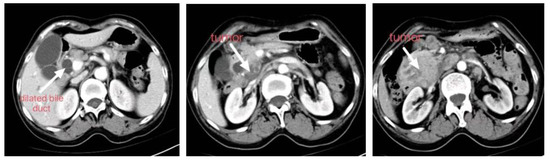

A 64-year-old female patient was admitted with obstructive jaundice. MRCP showed an irregular soft tissue mass in the descending duodenum, approximately 5.3 × 5.0 cm, and a mildly dilated pancreatic duct. There were multiple enlarged lymph nodes adjacent to the abdominal aorta. The surgical plan was formulated according to the 2D images. Considering that the tumor originated from the duodenum, the tumor was poorly defined with the portal vein and inferior vena cava, excluding invasion, the proposed PD was not radical. The tumor volume was 50.15 mL. The tumor was considered to originate from the head of the pancreas and invade the duodenum, and there was a gap between the tumor and the portal vein, inferior vena cava and abdominal aorta, and no vascular invasion was seen. Multiple enlarged lymph nodes were seen next to the peri-pancreatic vessels, and radical surgery and lymph node dissection were feasible, as shown in Figure 3 and Figure 4. The tumor was located in the head of the pancreas and invaded the intestinal lumen of the duodenum. The size of the tumor was assessed in the preoperative 3D evaluation, and there were gaps between the tumor and the surrounding blood vessels. The intraoperative bleeding was 300 mL, without blood transfusion. The operation time was 240 min, without postoperative complications. Postoperative pathology showed pancreatic head adenocarcinoma, hypofractionated lymph nodes (0/15), with nerve invasion (Figure 5).

Figure 3. Enhanced CT scan of abdomen.